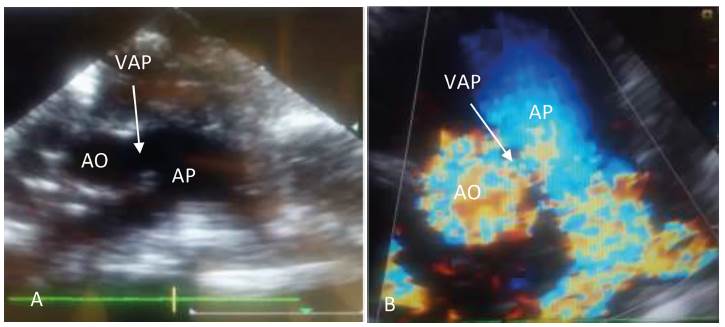

Figura 1 A. Ecocardiograma doppler bidimensional en plano paraesternal transversal de grandes vasos. B. VAP tipo I. AO: Arteria aorta. AP Arteria pulmonar

Figura 2 A. Ecocardiograma doppler bidimensional en plano paraesternal transversal de grandes vasos. B. VAP tipo I. AO: Arteria aorta. AP Arteria pulmonar. VAP: ventana aortopulmonar